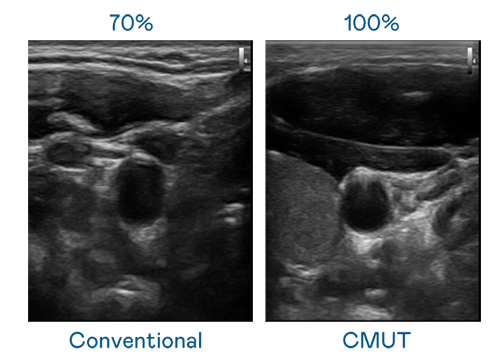

CMUT 技术是一种用电容式微机电元件来产生超音波讯号的技术。与传统 PZT 压电式技术相比,CMUT 频宽增加 30%,更宽频的超音波讯号让影像解析度大幅提升,是实现高影像品质医疗超音波扫描、促进精准医疗发展的关键技术。

超音波影像的解析度高低,首先取决于探头能发出的讯号频宽。1xBET CMUT 可提供高清晰的超音波讯号,提供高频宽、高灵敏度、影像纹理细节更高的超音波影像,协助医护人员缩短影像判读时间及利用精准的医疗影像进行诊断。